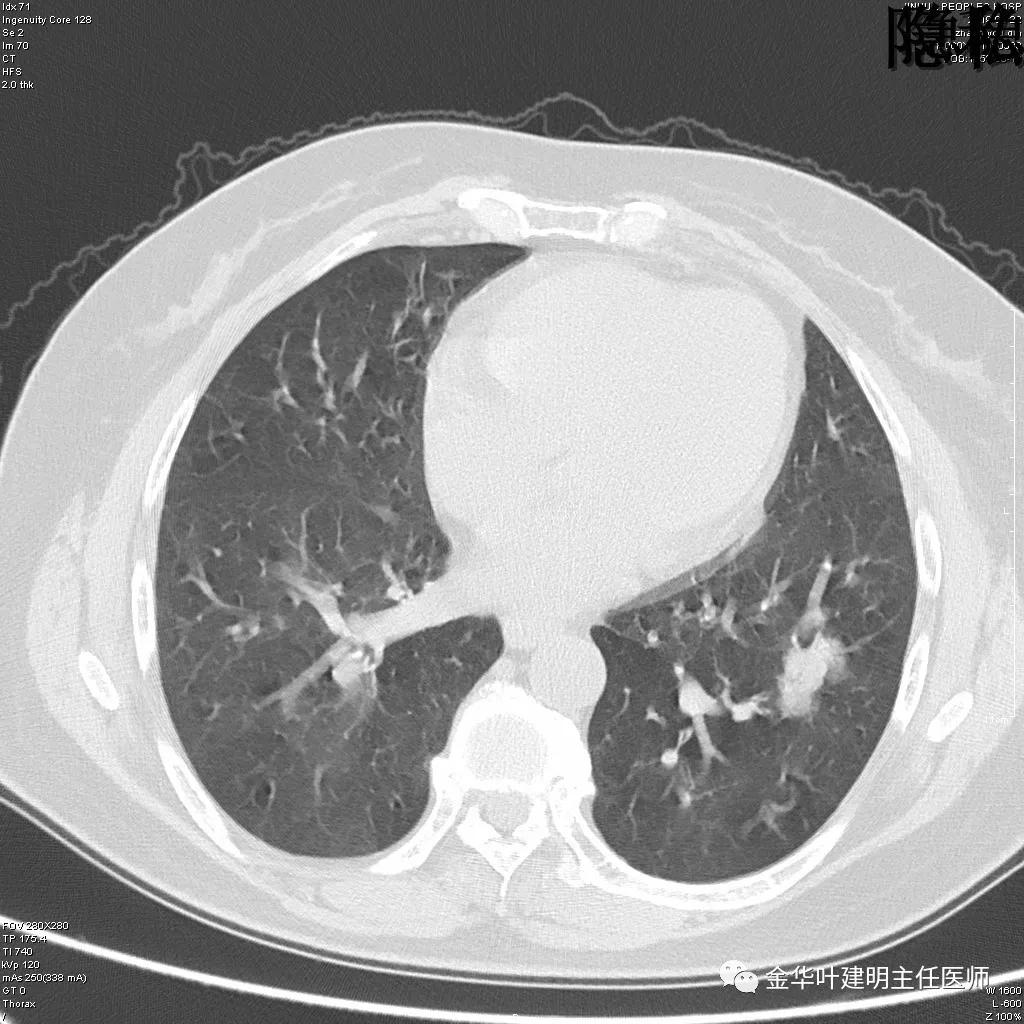

可见左肺下叶比较靠中央的部位也有一病灶,是混合磨玻璃影,偏实性,瘤肺边界清楚,是较为典型的肺癌表现。进一步的靶扫描图像如下:

靶扫描更清晰的显示细节,从影像上看,基本可以断定左下肺的是恶性肿瘤了,而且已经密度较高,长径也在3厘米以上,不能继续观察等待了!